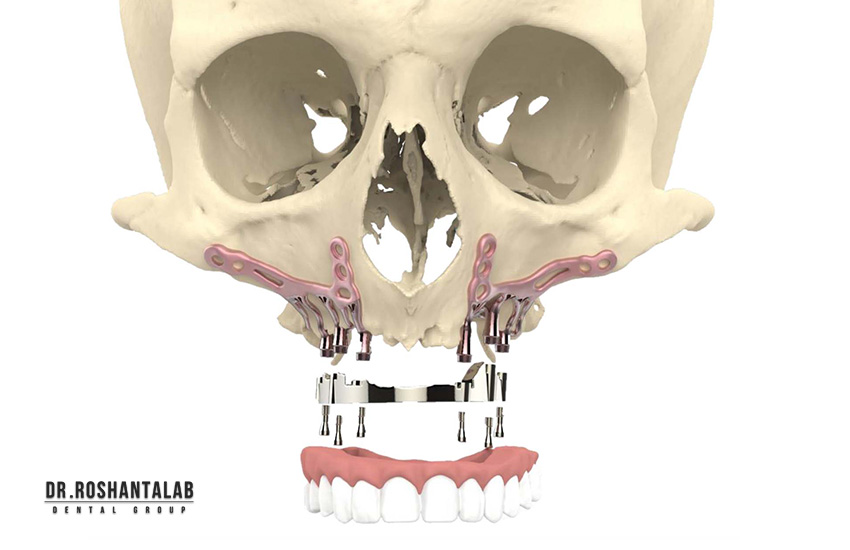

نوع ایمپلنت (مانند اندوستئال، سابپریوستئال یا مینی ایمپلنت) مستقیماً بر قیمت تأثیر میگذارد. ایمپلنتهای دیجیتال و ایمپلنت بدون جراحی (Flapless) که با استفاده از گایدهای سهبعدی انجام میشوند، گرانتر هستند. زیرا نیاز به تجهیزات پیشرفته مانند اسکنر CBCT دارند. ایمپلنت فوری (Immediate Loading) که روکش همان روز نصب میشود، هزینه بیشتری دارد نسبت به روش سنتی که ۳-۶ ماه زمان میبرد. همچنین، ایمپلنت All-on-4 برای فک کامل با ۴ پایه، قیمت کلی را کاهش میدهد.

تعداد دندانهای جایگزینشده مستقیماً قیمت را افزایش میدهد. برای یک دندان، اما برای چندین دندان (مثلاً ۳ دندان) ممکن است تخفیف پکیجی اعمال شود. در موارد فک کامل، روشهایی مانند All-on-6 با ۶ ایمپلنت انجام می شود. تعداد بیشتر ایمپلنتها نیاز به جراحی طولانیتر و مواد بیشتر دارد که هزینه را بالا میبرد.